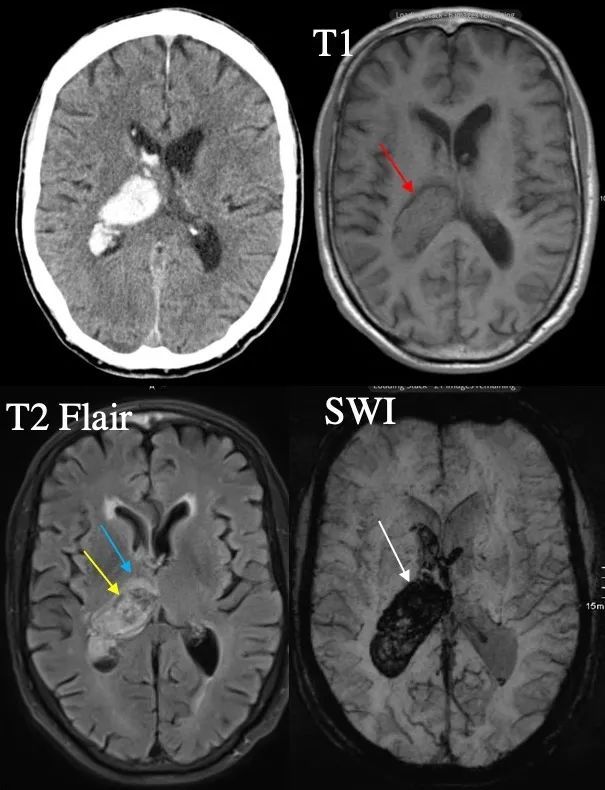

随后血凝块收缩 , 血浆析出 , 血肿在T1像信号逐渐升高至等信号 , 而血肿周边析出的血浆在T1像呈低信号环(图2:红箭) 。 在血肿与组织交界面的血液早期即迅速去氧化 , 成为去氧血红蛋白 , 在T2像呈低信号环(图2:黄箭) , 这是识别脑出血的一个首要征象 , 在SWI像上表现更为明显(信号范围明显大于实际体积 , 即磁敏感成像的开花效应)(图2:白箭) 。 另外血肿周围形成水肿 , 在T2像上呈高信号(图2:蓝箭) 。

文章插图

图2 60岁男性 , 左侧肢体偏瘫2小时(T1和T2双低信号环)(Radiopaedia , by Yves Leonard Voss)